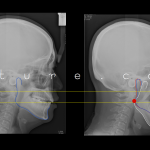

Profile